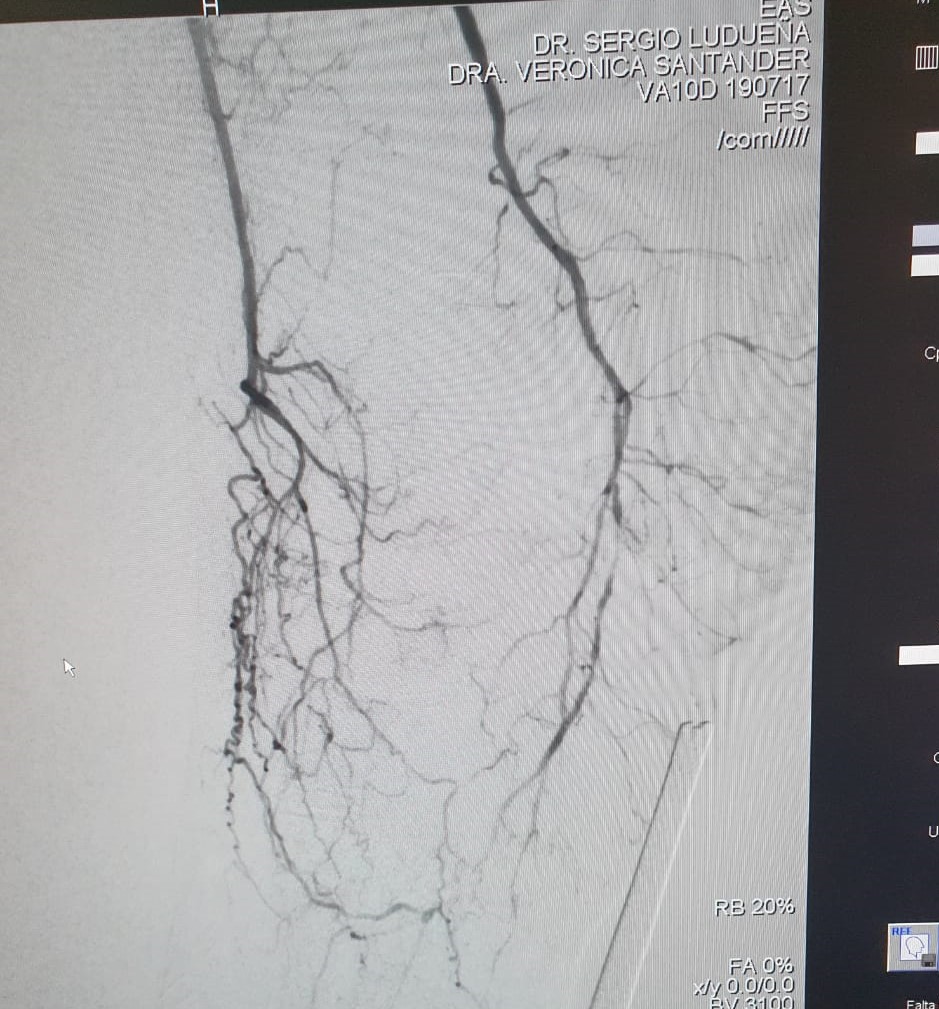

Se realizó un abordaje híbrido con el Dr. Alejandro Flores, y se re canalizó ambas arterias tíbiales. Procedimiento inédito en nuestra provincia.

Las imágenes siguientes son previas al procedimiento y posterior se ve ambas arterias tíbiales permeables, y circulación en el pie